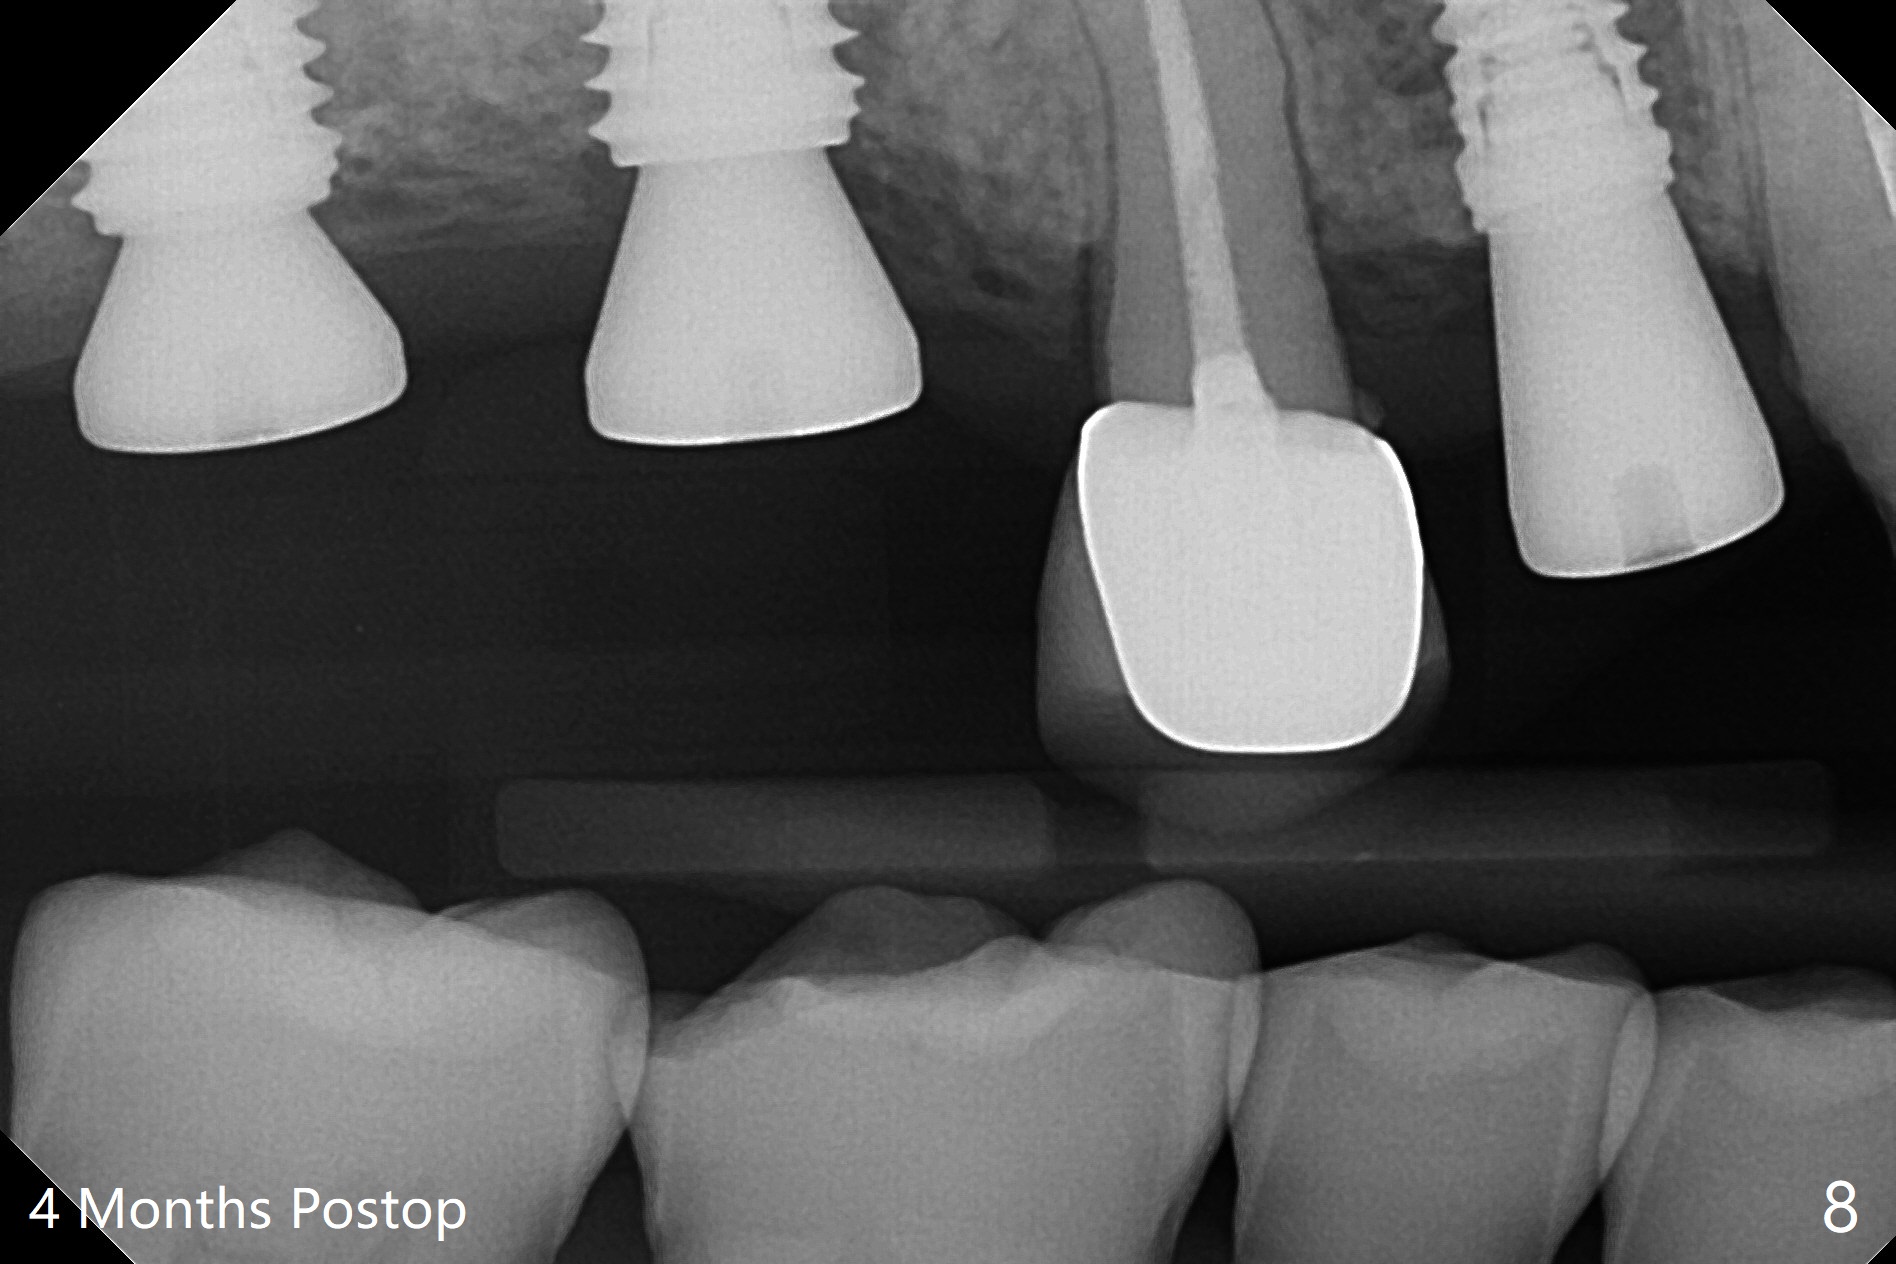

Two of 5x8.5 mm implants are placed at #2 and 3 with sinus lift using water ballooning technique; to avoid invading the neighboring root tips, an intraop PA is taken with a 2.2x11.5 mm drill at #5 (Fig.1). When a 2.5x11.5 mm 1-piece implant is placed at #7, there is 2.4 mm clearance from the impacted tooth (Fig.2). Following 1 mm deeper placement of the 1-piece implant, CT is taken to make sure that the threads are completely covered palatally (Fig.5 P). Interesting is that the sinus membrane is thickened at #2 and 3 (Fig.3 M), as compared to the clear sinus before surgery (Fig.3'). Bone graft is limited in the sinus (Fig.3 arrowheads). The implant at #5 (3.5x11.5 mm) is precisely placed subcrest bucco(B)-palatally (Fig.4). Since the limited field viewed CT does not cover the implant at #2 (Fig.3), immediate postop PA is taken (Fig.6). In fact all of the implants are placed subcrestal, as shown by intraoral X-ray 4 months postop (Fig.7-9). The abutments at #2, 3 and 5 are retorqued (30 Ncm) after crowns' try in and adjustment (Fig.10,11). There is a vertical gap between the implant and abutment at #2 (Fig.11 ^) and a horizontal one at #5 (<). There is apparently no bone loss 1 year 5 months post cementation (Fig.12).